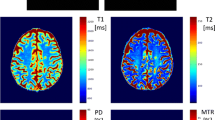

It has previously been demonstrated that MS pathology can be described through quantitative spatial mapping of MRI-derived relaxometry parameters, such as longitudinal (T1) and transverse (T2) relaxation times or proton density (PD) [8]. Further, parametric mapping may overcome the aforementioned limitations associated with MS diagnosis and staging by improving diagnostic accuracy [6, 9, 10] and predicting patient functional impairment [11, 12].

MRF is a novel MRI technique that allows quantitative mapping of T1, T2 and PD using acquisition schemes followed by matching of the data to synthetically generated signals. The details of MRF have been described previously [13] and involve the repeated acquisition of image data over a time course in which acquisition parameters such as the flip angle, pulse repetition rate (TR) and echo time (TE) are intentionally modified [13]. Because the resultant time evolution of the signal in a given voxel is unique for a certain combination of tissue MR properties such as PD, T1 and T2, MRF derived estimates of these parameters are generated by comparing the signal evolution history of a given voxel to a dictionary of pre-simulated signal evolutions [14].

All clinical data were acquired on two 3T MR scanners (Discovery MR750 and Discovery MR750W, GE Healthcare, Waukesha, WI) using an eight channel receive-only RF head coil. MRF data acquisition was performed using a 3D steady state free precession (SSFP) sequence with a multi-axis spiral trajectory [17]. Adiabatic inversion pulses were used before each acquisition. The flip angle ramped schedule ranged from 0.778° to 70°. Sequence details can be found in [17,18,19]. The acquisition FOV was 25.6 × 25.6 × 25.6 cm3 with 1mm isotropic voxel resolution. The total acquisition time for the whole brain volume was 4 min 38 s. The T1 range for the dictionary was from 10 to 3000 ms and T2 from 10 ms to 2000 ms. Fingerprint reconstruction and dictionary matching were performed offline using Matlab (Mathworks, Natick, Massachusetts) on a 64bit Linux workstation equipped with two 8‐core Intel Xeon Gold 6244 CPU @ 3.60 GHz, 376 GB system memory, and NVIDIA Tesla V100 GPU. The reconstruction pipeline has been described elsewhere [20].

A representative MRF-based T1 map paired with conventional weighted imaging is shown in Fig. 2.